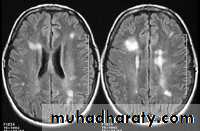

- the most characteristic appearance is that of peri ventricular nodular Hyper intense lesions on T2 weighted images.

-the plaques are also well seen at the gray- white matter interfaces.

-multiple cerebral lesions are seen in over half the patient presenting with a single episode of optic neuritis.

-some lesion may show a central area of greater signal intensity , resembling a target.

-differential diagnosis :1-ischaemic lesions ,2-following radiotherapy , 3- in encephalomyelitis.

SAGITAL FLUID ATTENUATION INVERSION RECOVERY SEQUENCE: OVOID PLAQUES ( HIGH SIGNAL INTENSITY) , WHICH ARE PERPENDICULAR TO LATERAL VENTRICLE.